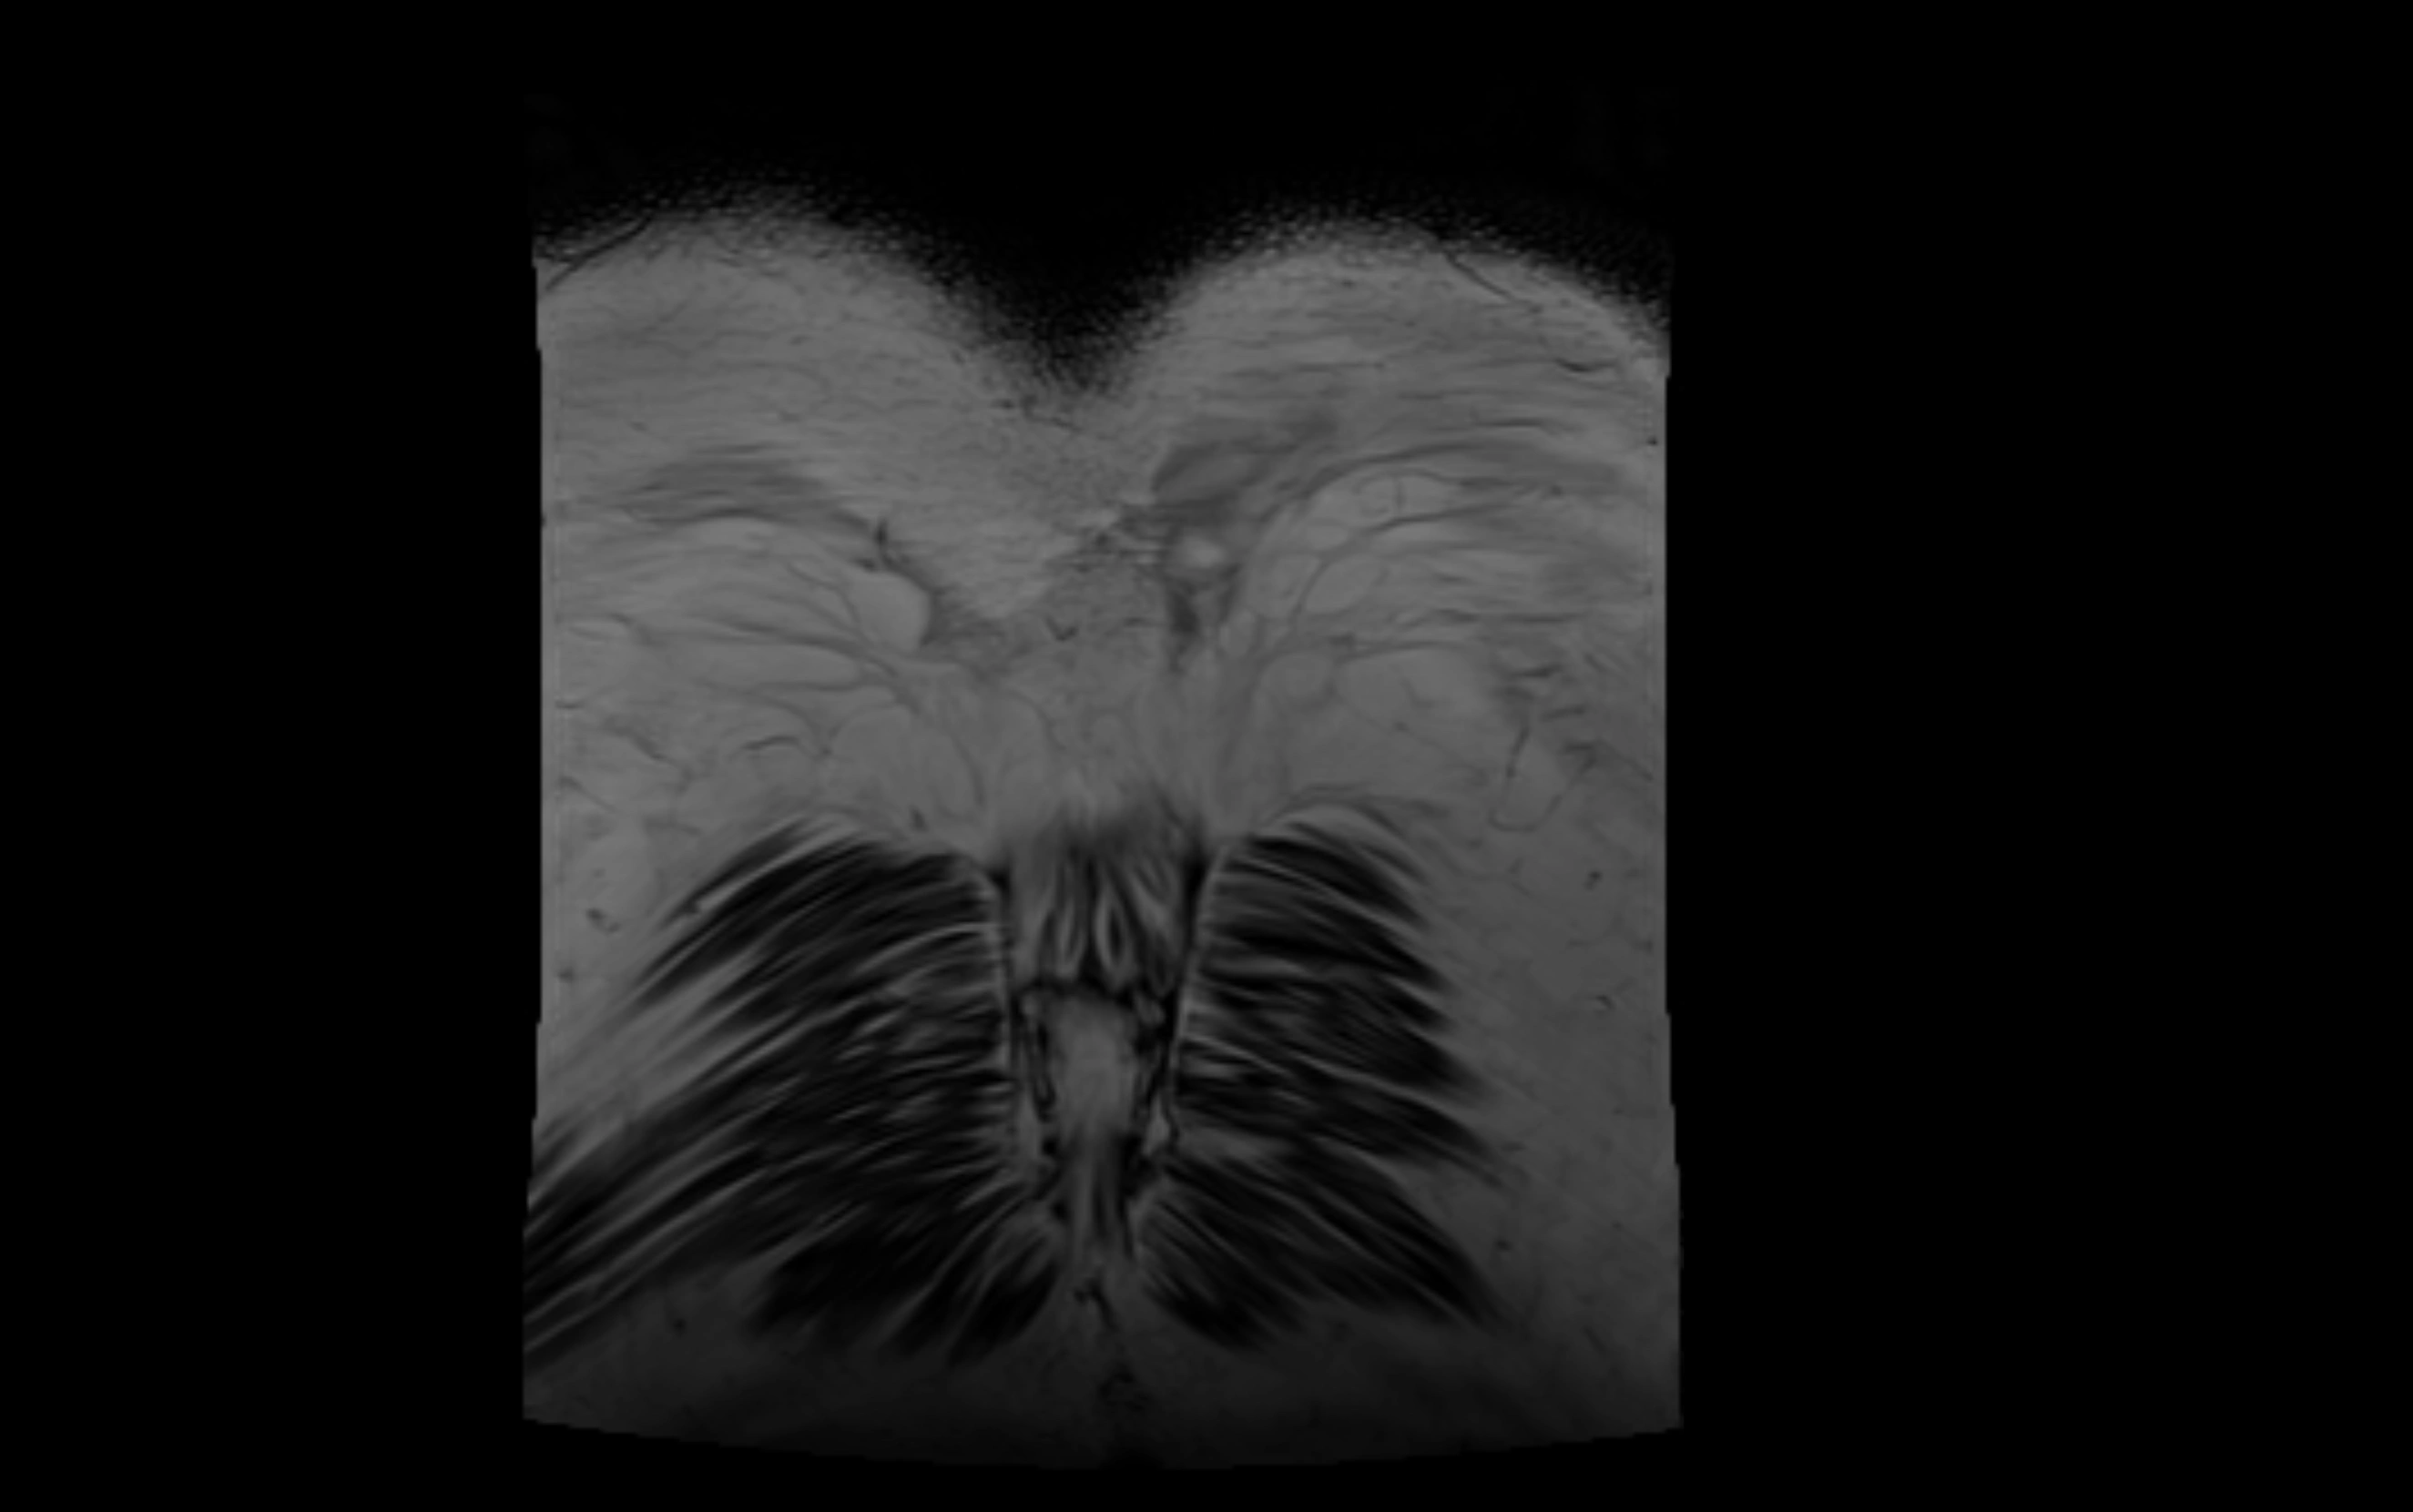

MRI image

image